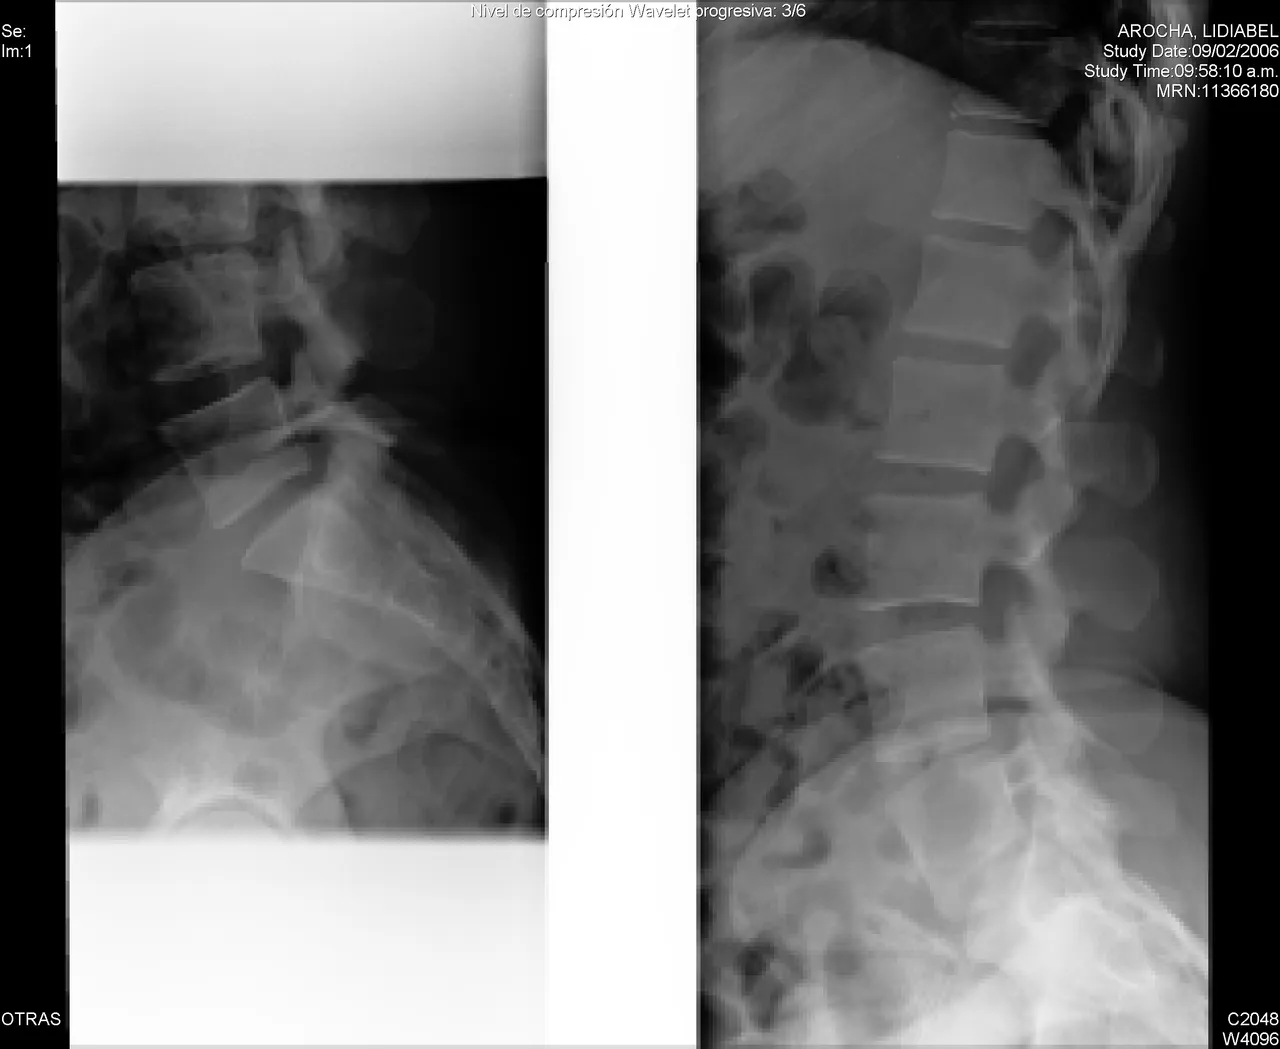

A spinal fracture (spinal compression fracture) occurs when one of the bones in the spine fractures or collapses.

These fractures occur most often in the fifth vertebra of the spine or lumbar spine, although they can also occur in the fourth lumbar vertebra. Fractures may occur on one or both sides of the pars bones. In more severe cases, spondylolisthesis may develop. This occurs when a fractured pars bone separates, allowing the injured vertebra to move forward.

Unfortunately, having a spinal fracture greatly increases your chances of having another one. Over time, multiple fractures can affect the alignment of your spine and cause it to lean forward (Dowager's hump).

This forward curvature can become so pronounced that it will affect your balance and compress your chest cavity, making it difficult to breathe, eat, or sleep properly. Other risk factors include your age, gender and lifestyle.